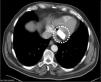

Paciente de 79 años, con AP de tumor torácico. Ingresó por síndrome coronario agudo con elevación de ST (SCACEST) secundario a enfermedad de 3 vasos, precisando revascularización. En la ecocardiografía transtorácica (ETT) se objetivó, a nivel de válvula mitral, una imagen hiperecogénica con ecolucencia interior adherida al velo posterior, de aproximadamente 3×3mm que no comprometía el llenado mitral, pero sí dejaba insuficiencia mitral leve (fig. 1). Se descartó, por las características morfológicas, TAC y contexto clínico: tumoración, verruga, absceso o trombo a nivel mitral, diagnosticándose de degeneración caseosa de la válvula mitral (DCAM) (fig. 2). La DCAM es un hallazgo infrecuente observado de forma casual tras una ETT; suele ser asintomática, aunque puede provocar complicaciones inesperadas y graves, su tratamiento es habitualmente conservador.

ETT: En la imagen de la izquierda (plano longitudinal eje largo de VI) se observa una gran tumoración dependiente del velo posterior de la válvula mitral (flechas), de aspecto hiperecogénico de márgenes bien definidos con ecolucencia interior correspondiente a una DCAM. En la figura de la derecha (plano longitudinal eje corto del VI) se aprecia como la imagen descrita afecta exclusivamente al velo posterior de la válvula (flecha).